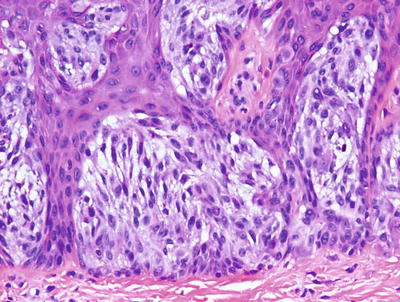

Fig. 20.13

Nevus spilus is characterized by epidermal changes that resemble those seen in a lentigo simplex in some areas, and a junctional nevus in others. In some foci, a dermal melanocytic proliferation is present